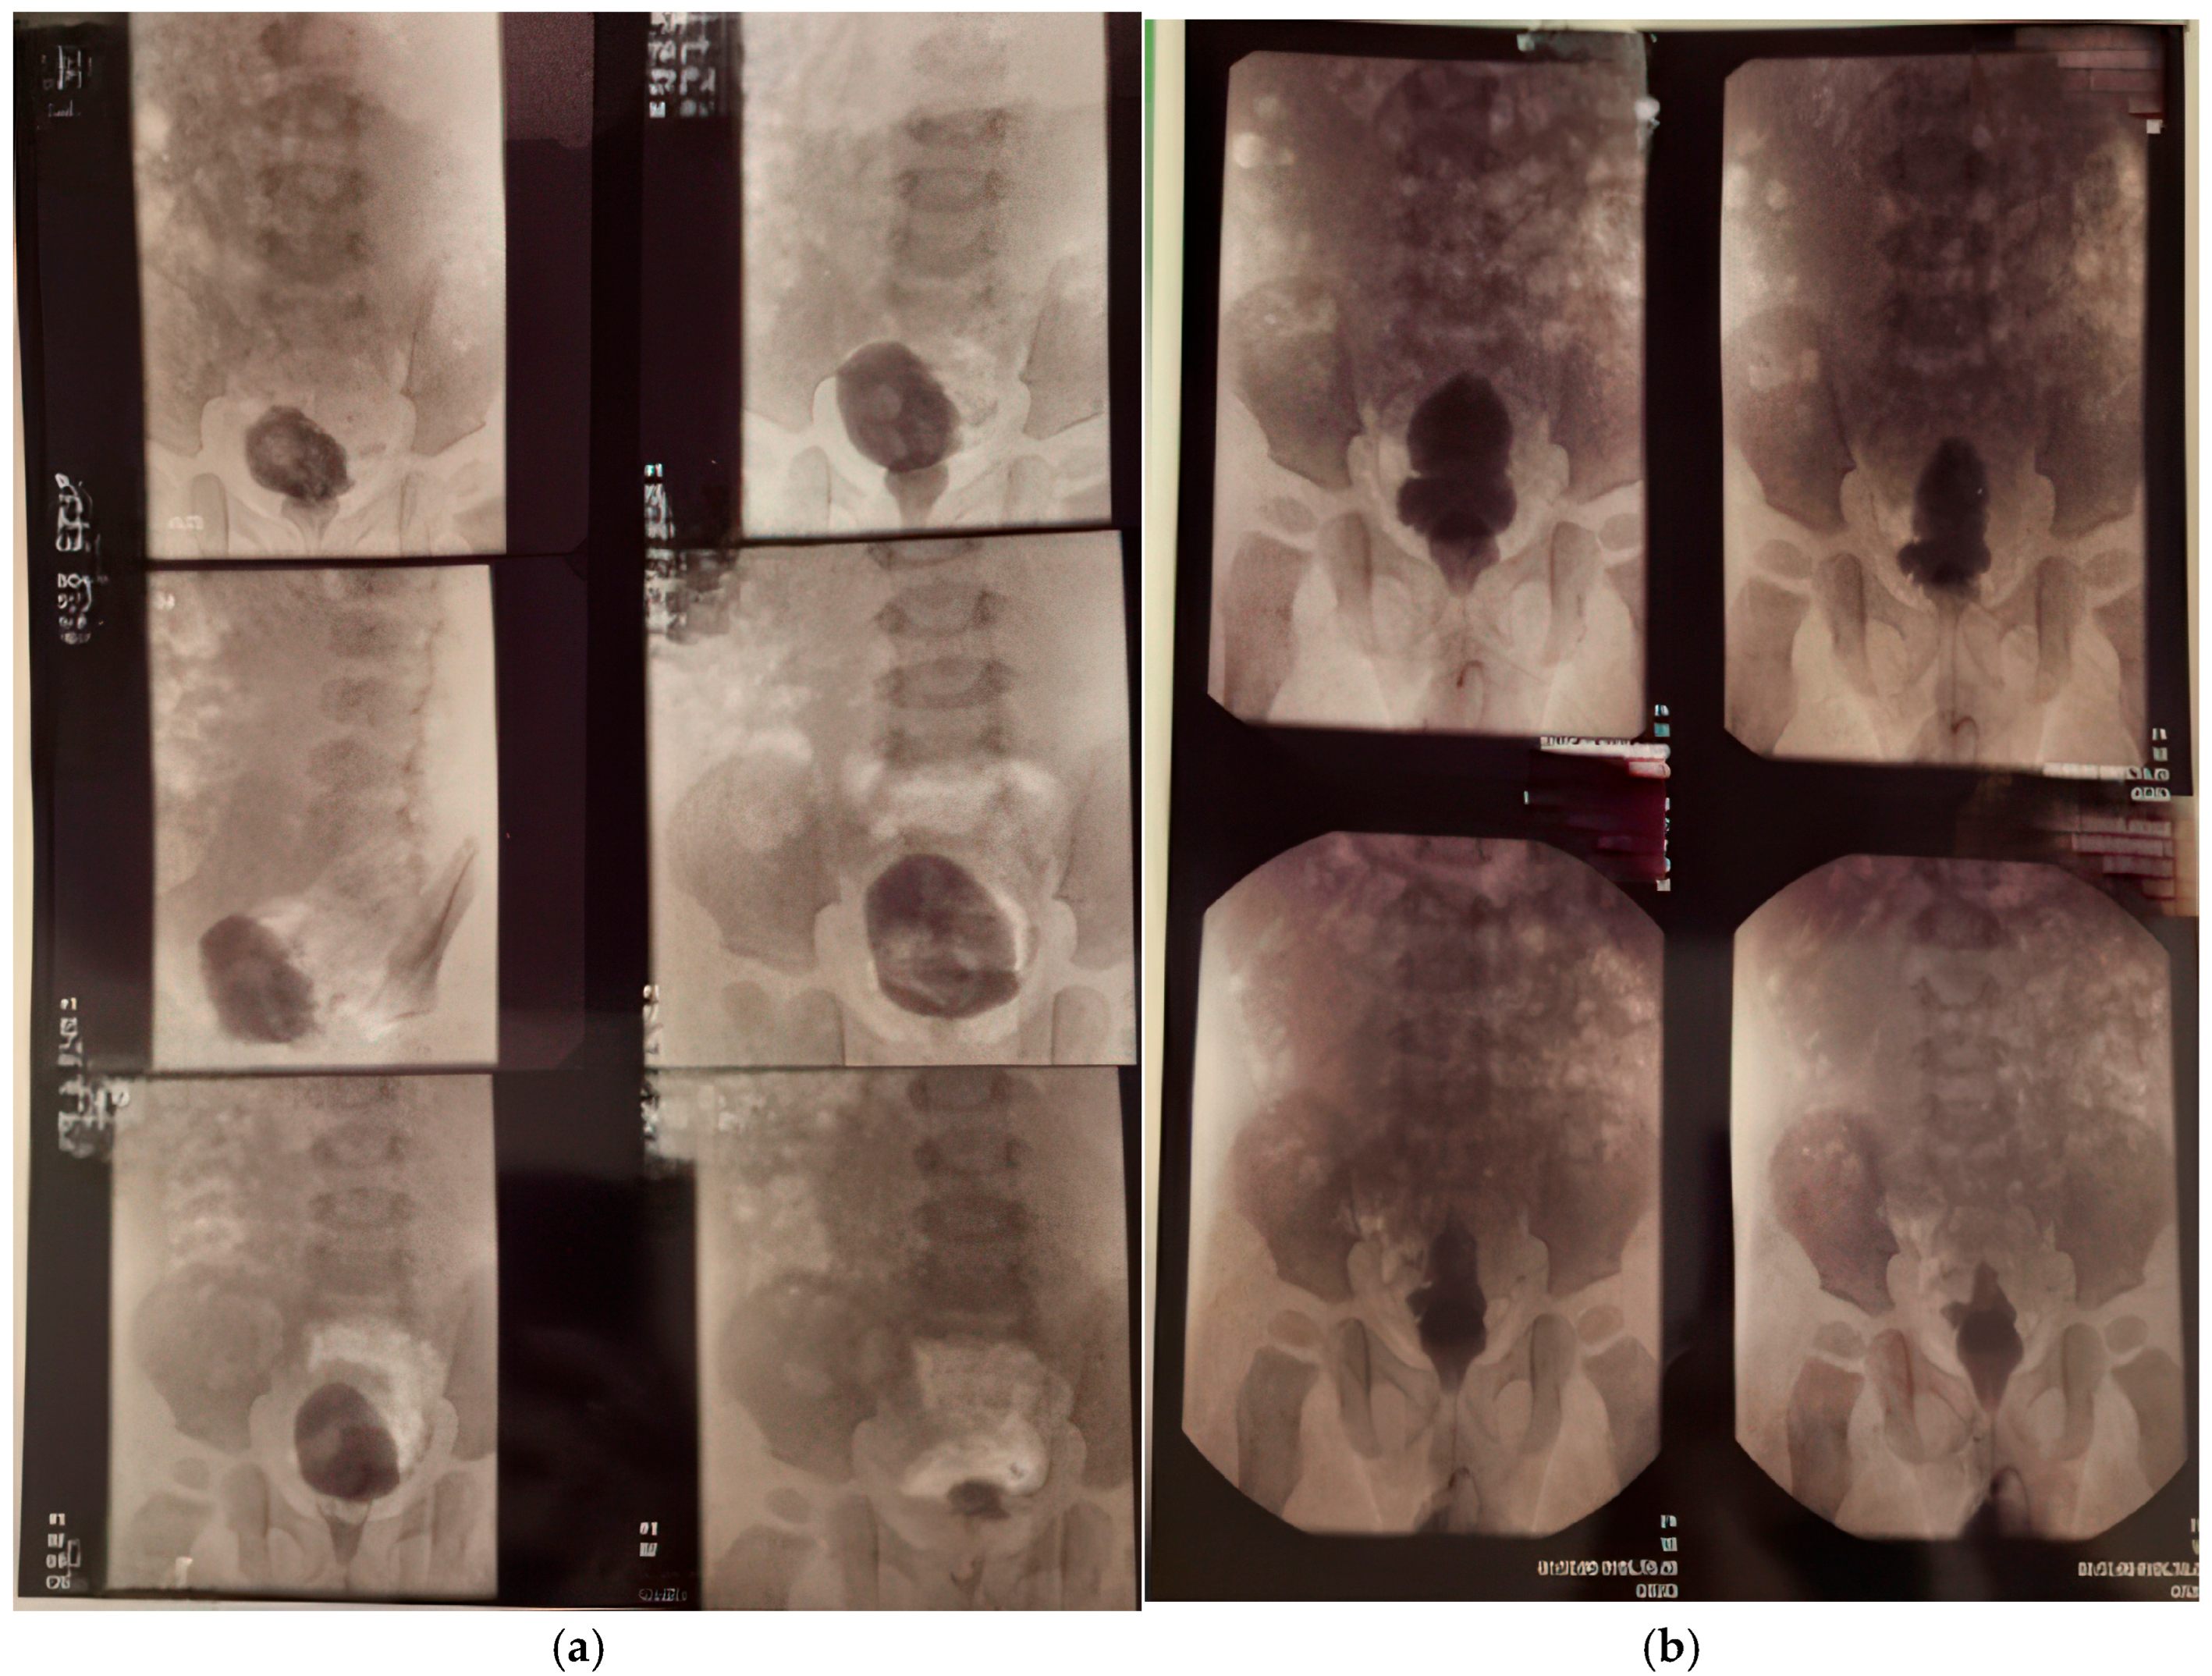

The first cystography was performed at 1 month and 20 days of life (Figure 3a, imaging on the left side). Findings: bilateral ureterostomy. Bladder in normal position, reduced in size, with smooth but slightly lobulated contours, and homogeneously opacified. Passive and active vesicoureteral reflux on the left side.

Figure 3.

Cistography evaluation at two time points. (a) At 1 month and 20 days (b) At 1 year, 4 months, and 25 days (2 months post-surgery).

At 1 year, 4 months, and 25 days of life, voiding cystourethrography was performed at 2 months distances from the surgery. The second cystography was showing an irregular, pseudo-diverticular contour of the urinary bladder and a thickened bladder neck. No vesicoureteral reflux or post-void residual urine was identified (Figure 3b, imaging on the right side).